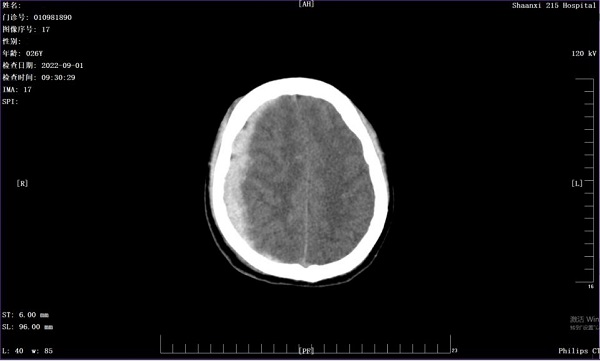

三个月前,26岁的张先生不慎被汽车撞倒,立即陷入昏迷,急诊送入陕健医二一五医院救治。入院后CT检查发现,张先生的右侧硬膜下大量出血,诊断为急性右侧硬膜下脑出血伴脑疝形成,病情十分危重。

(入院急诊头颅CT)